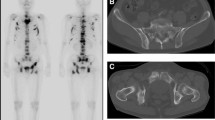

Usefulness of whole-body bone scintigraphy in osteomalacia. Anterior (left) and posterior (right) whole-body scans in a 77-year-old man with primary hyperparathyroidism show generally increased skeletal uptake due to osteodystrophy with avaricious tracer uptake. Note the well-functioning left kidney

Hepatic osteodystrophy with systemic osteoporosis. (a) Anterior (left) and posterior (right) whole-body bone scans in a 60-year-old man with alcoholic hepatopathy shows generalized low uptake with numerous bone infractions (arrowheads). (b) Anterior radiograph of the pelvis reveals a typical infraction in the lateral cortex of the right proximal femoral shaft (courtesy of Dr. H. Ohta, Department of Radiology, Osaka Medical School, Japan)